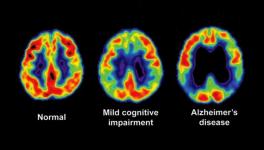

Out of the many possible variables studied by the researchers, it was found that performance deficiency on a brief cognitive screening test focussed towards orientation was found to be the most significant one. This variable was found to have accounted for about 20% of the variance in life expectancy. This was followed by other factors like sex, age, race or ethnicity and also included neuropsychiatric symptoms, functional impairment ratings, etc.

Explaining the results of the analyses, Schaffert said, “We found that beyond global cognitive function, patients who were older, non-Hispanic, male and who had more motor and psychiatric symptoms had a significantly shorter life expectancy.”

These also included the presence of abnormal aggregation of proteins. It is well known that dementia patients, especially in Alzheimer’s disease, have an abnormal aggregation of a particular protein named beta amyloid, which has not been fully understood yet despite extensive research. In the study group, life expectancy ranged from one month to 130 months after the diagnosis of Alzheimer’s—most of the individuals in the study group were diagnosed on their first visit.